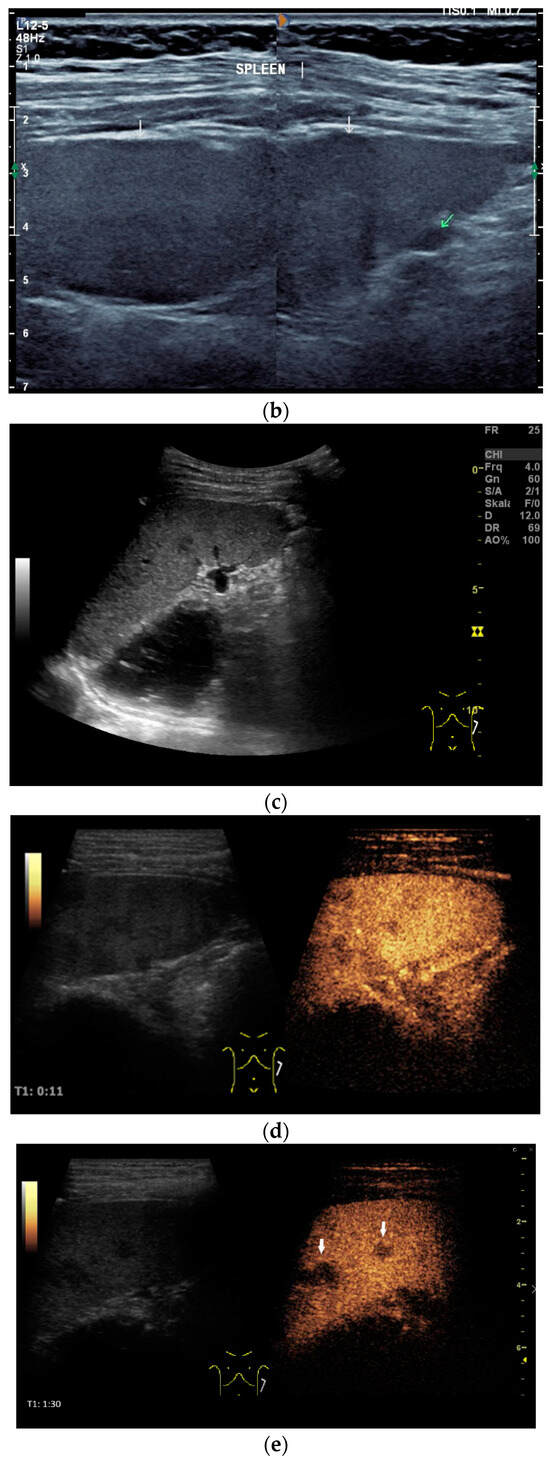

Figure 6.

A case of esophageal tuberculosis. A 52-year-old male non-smoker presented with progressive dysphagia and weight loss (15 kg in 6 months). Upper GI endoscopy revealed two subepithelial esophageal masses covered by normal mucosa (a). A CT scan showed large solid mass lesions in the mediastinum, with small gaseous inclusions (arrowhead) and a thickened esophageal wall (b, arrow). EUS ruled out a subepithelial esophageal tumor, and confirmed a large mediastinal hypoechoic mass infiltrating the esophageal wall, which was up to 12 mm thick with a complete loss of layering (c). Multiple enlarged and confluent hypoechoic lymph nodes were found throughout the mediastinum (d). Contrast-enhanced harmonic EUS showed the hyperenhancement of the mediastinal mass lesion and the thickened esophageal wall with some anechoic necrotic parts (*), and echogenic gaseous reflections (arrow; e). EUS-FNA (22 Gauge) of lymph nodes and of the thickened wall was performed (f; needle is marked with an arrowhead). Turbid fluid was aspirated from one lymph node, and then sent for cytological and microbiological examination and polymerase chain reaction (PCR) for mycobacteria. Positive Ziehl–Neelsen staining and PCR for mycobacterium tuberculosis and cheesy, necrotizing granulomas (g), cytology, Papanicolaou stain: giant cell; (h), histology, hematoxylin-eosin stain: necrotizing granulomas; courtesy Gunnar Schröder, Institute for Pathology Wildau, Germany) established the diagnosis of extrapulmonary tuberculosis involving the mediastinum and esophagus. Bronchoscopy revealed a fistula opening in the left main bronchus marked by the black arrow (i).